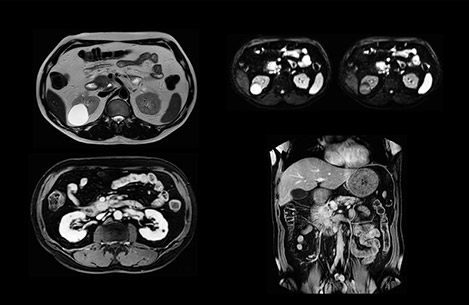

Comparison of liver MRI with and without MultiVane XD motion correction

In this example the image quality of the MultiVane XD images is evidently better than in the images without MultiVane XD. Ingenia 1.5T with dS Torso coil solution.

“We include mDIXON for the dynamic sequences because of the robust and homogeneous fat suppression we get with that. We had been using eTHRIVE, but we are now quite happy with mDIXON. Sometimes we use a medication to calm the bowels, to further improve the image quality.”